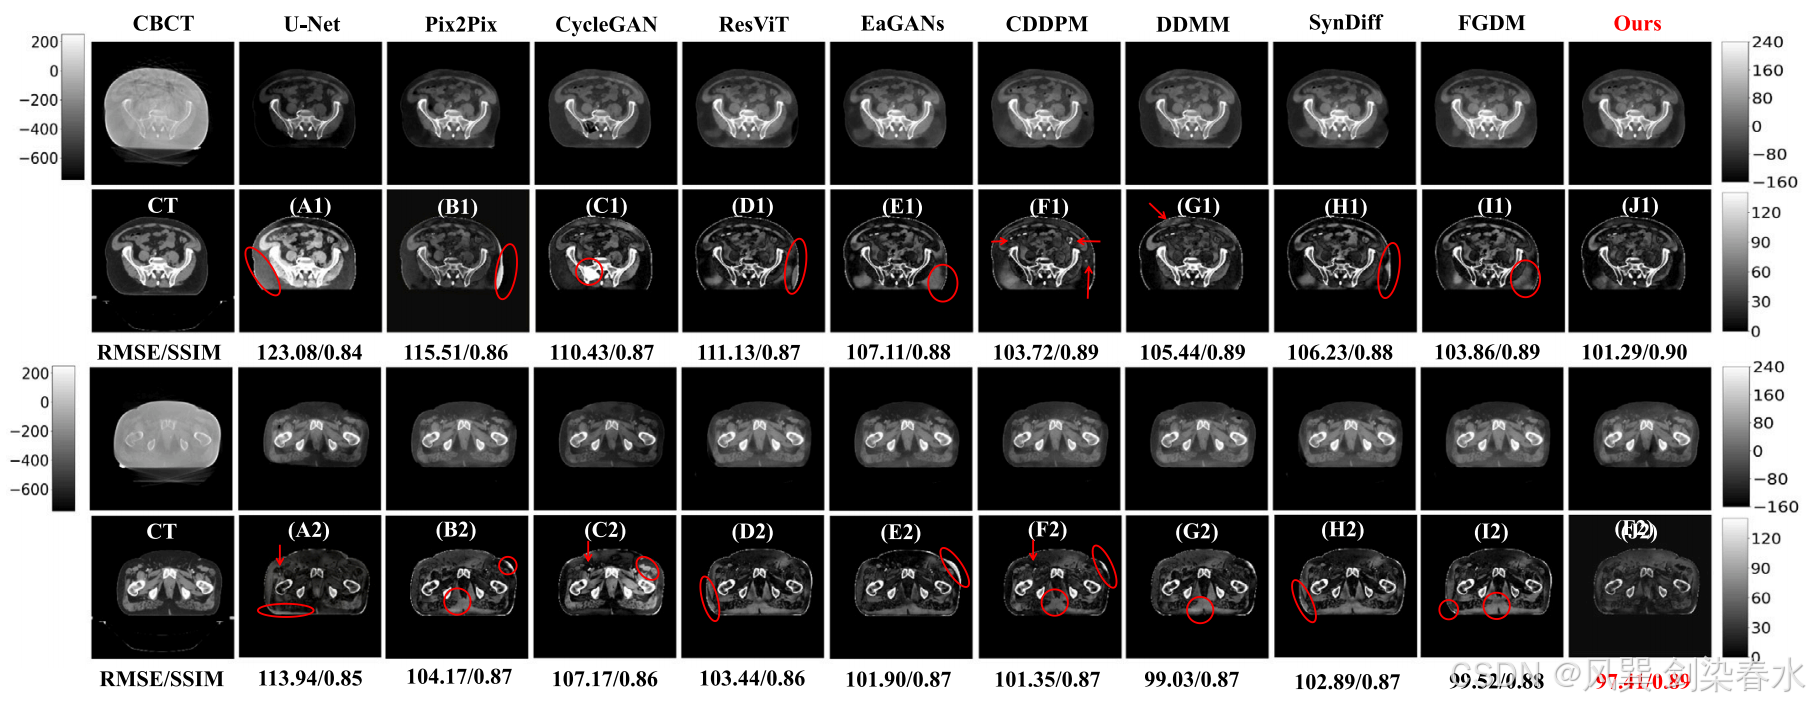

Figure 4 | 外部骨盆测试数据集可视化:(A1-J1)和(A2-J2)是 CT 与相应预测的 sCT 之间的绝对差异图像,CBCT 的显示窗口在外部测试数据集中为 [−750,250] HU,而 CT 和 sCT 的显示窗口则为 [−160,240] HU;